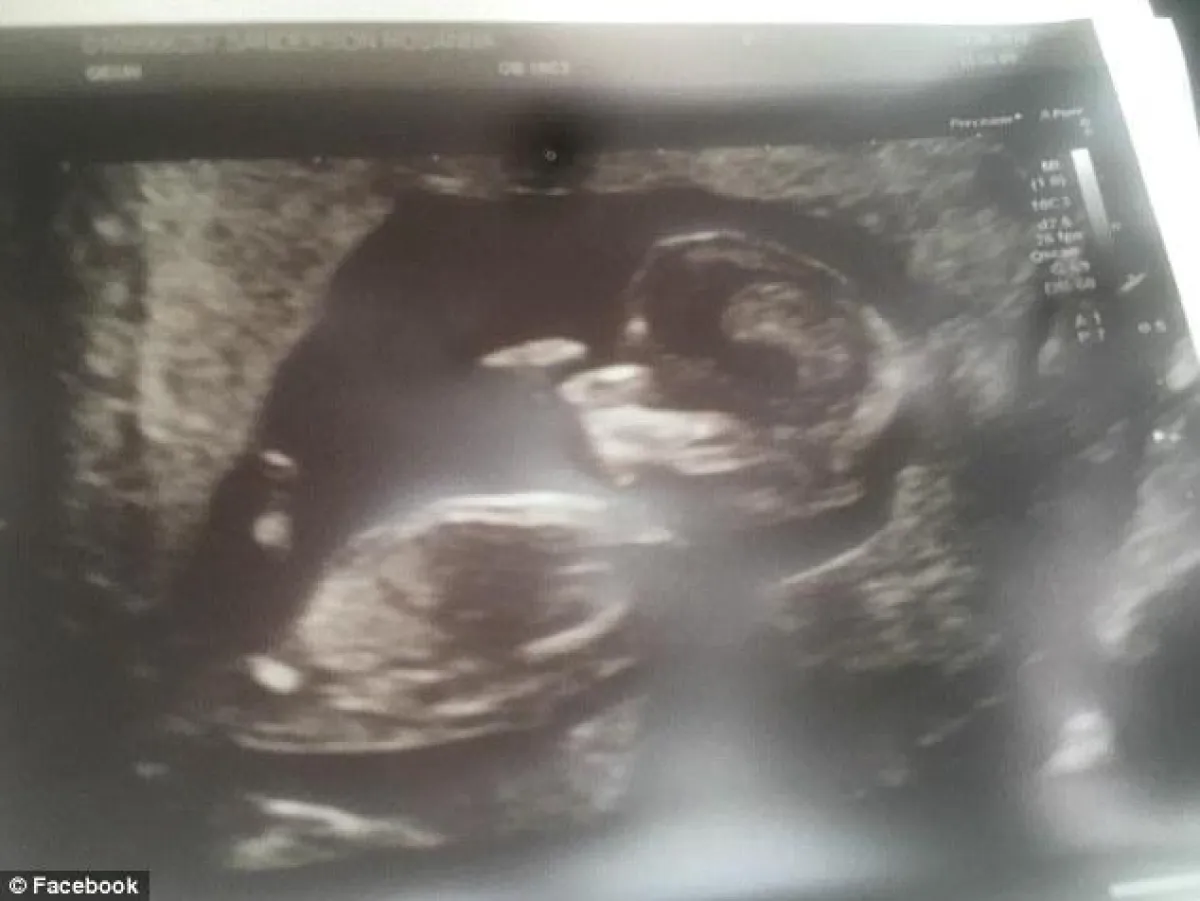

أولى خطوات "روزانا"، التي كانت تعمل مصففة للشعر، والتي كانت تبلغ من العمر 22 عاماً، نحو حلمها بأن تكون أمّاً، بدأت تتحقق بتاريخ 27 آب / أغسطس الماضي 2018، حين ذهبت برفقة والدتها "جاكلين" لإجراء اختبار للحمل، حينها كان يملأها الخوف والأمل والقلق، وخيط من الفرح في حال كانت النتيجة إيجابية، وما أن دخل الطبيب وبدأ عمله، وظهرت صورة رحمها على الشاشة، وهي تحمل طفلها الموعود، كان الفرح يكاد يقفز من قبلها وعينيها ويملأ المكان.

وفي حديث "جاكلين" لصحيفة الـ"ديلي ميل" البريطانية، قالت بأن كل ما كانت تطلبه ابنتها، هو أن تصير أمّاً فقط، وكانت تتوقع معرفة جنس جنينها قريباً هي وزوجها أوليفر الذي يبلغ من العمر 28 عاماً، وتابعت جاكلين قائلةً: "لقد كانت روزانا في قمة حماستها، فقد كانت حاملاً في الأسبوع الـ14، وكان من المفترض أن يولد طفلها في شهر آذار / مارس القادم 2019، وتحقق حلمها الذي لطالما حلمت به أخيراً، وظلت تردد طوال الوقت، بأن (هذا الطفل سيكون لي، هذا الطفل سيجعلني أشعر بالكمال أخيراً، هذا الطفل سيجعلني أفضل يا أمي من أي وقت مضى)، لقد كانت سعيدة للغاية وبشكل لا يُصدق".